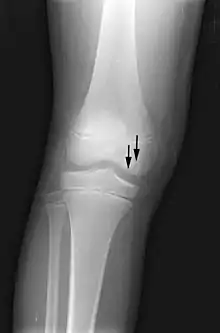

In the early stages, bone scintigraphy and MRI are the preferred diagnostic tools.[18][19]

X-ray images of avascular necrosis in the early stages usually appear normal. In later stages it appears relatively more radio-opaque due to the nearby living bone becoming resorbed secondary to reactive hyperemia.[2] The necrotic bone itself does not show increased radiographic opacity, as dead bone cannot undergo bone resorption which is carried out by living osteoclasts.[2] Late radiographic signs also include a radiolucency area following the collapse of subchondral bone (crescent sign) and ringed regions of radiodensity resulting from saponification and calcification of marrow fat following medullary infarcts.

The intravertebral vacuum cleft sign (at white arrow) is a sign of avascular necrosis. Avascular necrosis of a vertebral body after a vertebral compression fracture is called Kümmel's disease.[20]